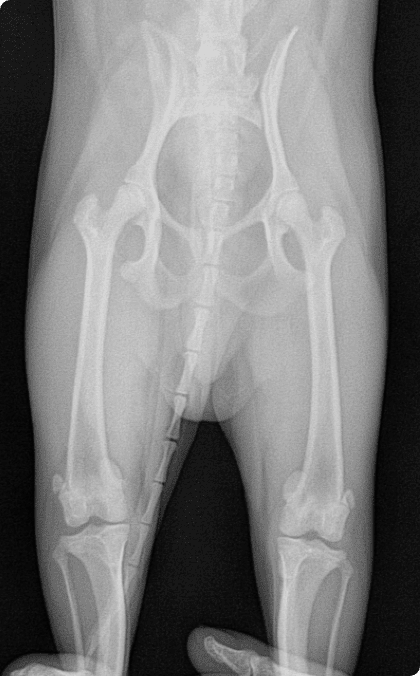

선천적 탈구부터 퇴행성 관절질환까지 다양한 고관절 문제를

통증은 최소화하고 재발 방지와 기능 회복에 집중합니다.

대퇴골 도르래 고랑에서 슬개골이 이탈되는 질환으로

소형견에서 가장 흔히 발생하는 관절 질환.

수술적 교정이 이루어지지 않으면

관절염 악화, 십자인대 파열, 골 변형으로 이어질 수 있음.